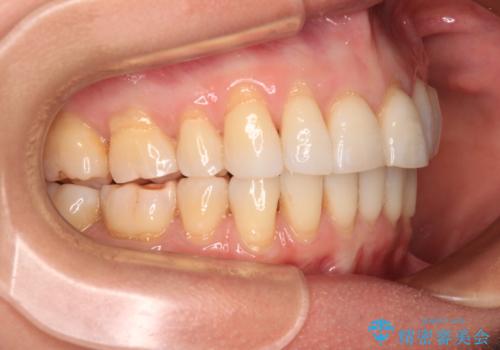

後戻りで突出した口元を引っ込めたい インビザライン矯正治療

- 上の前歯の出っ歯を治したいとのことで来院された患者様です。

後戻りによる再矯正というもともあり、インビザラインを希望されていました。

上顎の歯は後方移動とIPR(歯と歯の間を削る)によって口元が引っ込むように、下顎は歯列全体の拡大とIPRによって上顎とバランスよく咬み合うように設計し、インビザラインにより治療を行うこととしました。

治療を開始して暫くして、勤務先から2年以上帰国することができず、それまでの移動がほとんど後戻りしてしまい、帰国後に再度後戻りをリカバリーするための治療を行うこととなりました。

5年以上の治療期間がかかりましたが、気になっている部分を改善することができました。